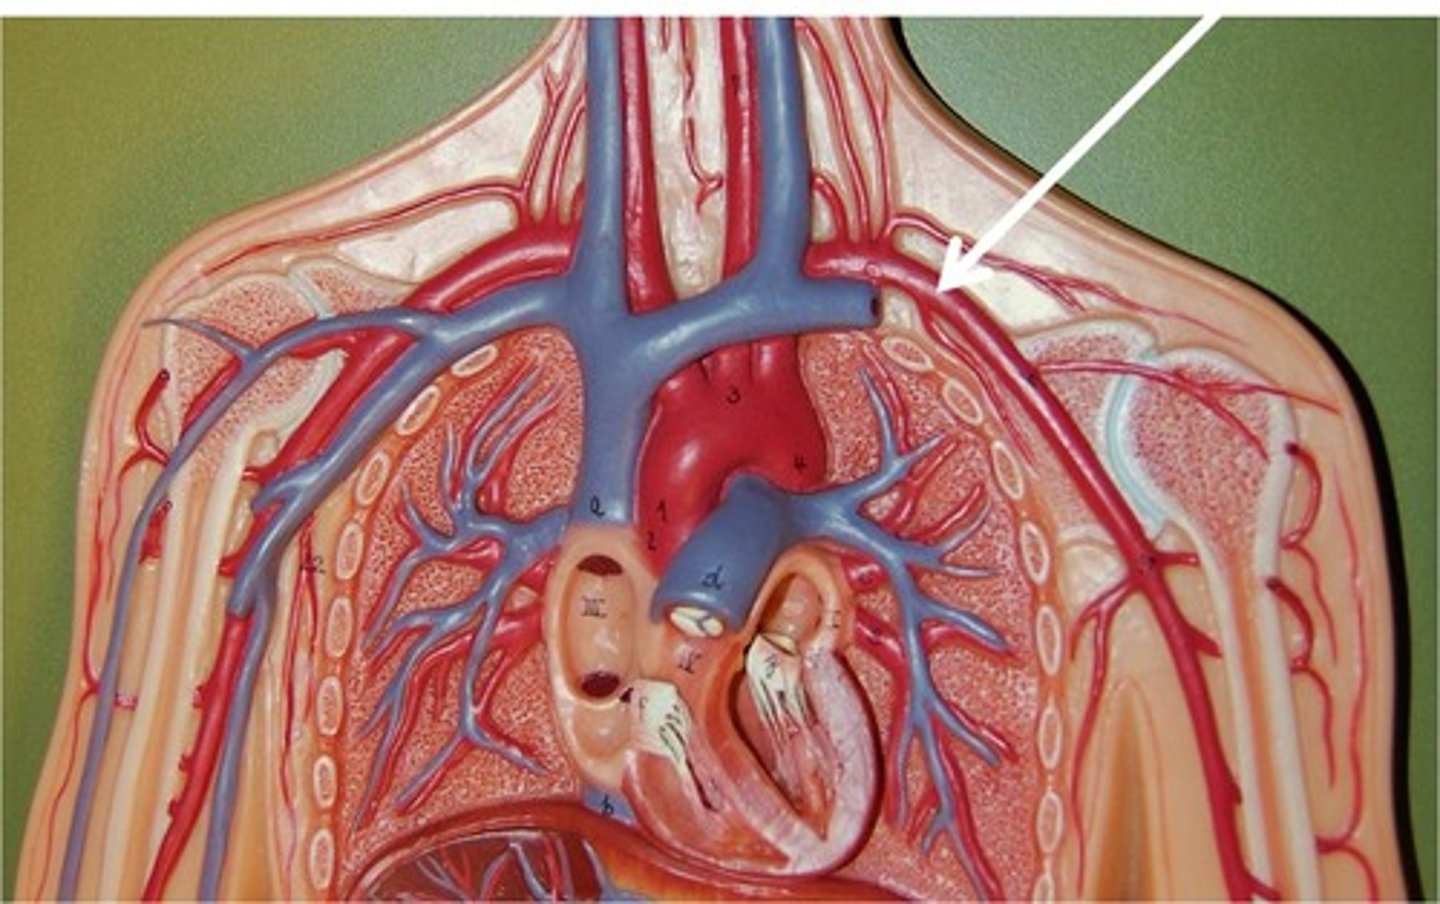

Right common carotid artery

left common carotid artery

right subclavian artery

left subclavian artery

brachiocephalic artery

feeds right common carotid artery and right subclavian artery

aortic arch

feeds brachiocephalic artery, right and left common carotid arteries, right and left subclavian arteries

axillary artery

flows into axilla, lateral chest, and shoulder joint

brachiocephalic vein

subclavian vein

superior vena cava